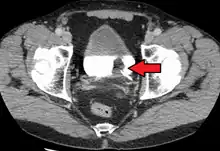

| Transitional cell carcinoma of the bladder. The white in the bladder is contrast. | |